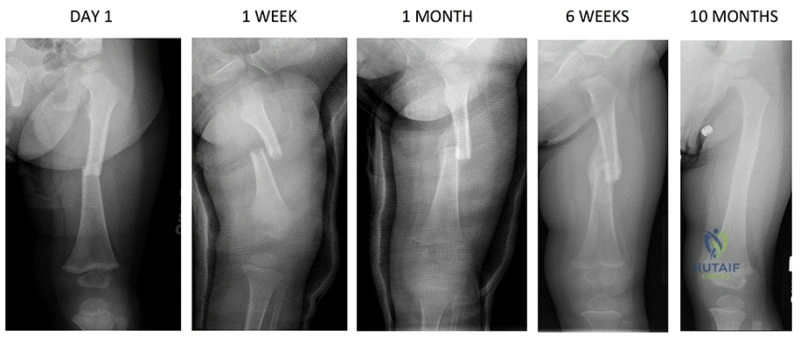

Secondary (indirect) bone healing is the natural physiological pathway and occurs under conditions of relative stability (strain between two and ten percent). This is seen with conservative management (casting, bracing) or flexible surgical constructs (intramedullary nails, bridge plates, external fixators). Secondary healing progresses through four overlapping phases. The initial inflammatory phase involves hematoma formation, macrophage infiltration, and the release of osteoinductive cytokines (Interleukin-1, Interleukin-6, Tumor Necrosis Factor-alpha). This is followed by the soft callus phase, characterized by chondrogenesis and the formation of a cartilaginous scaffold. The hard callus phase involves endochondral ossification, where the cartilage is mineralized and replaced by woven bone. Finally, the remodeling phase, governed by Wolff's Law, converts the woven bone into mature lamellar bone oriented along the lines of mechanical stress.

Post Operative Rehabilitation Protocols

For fractures treated with absolute stability (e.g., articular fractures fixed with lag screws and plates), the construct relies entirely on the implant to withstand physiological loads until primary healing occurs. Because primary healing is slow and there is no protective callus, early aggressive weight-bearing can lead to catastrophic implant failure. However, early active range of motion of the adjacent joints is mandatory to prevent capsular contracture and promote cartilage nutrition. Therefore, these patients typically undergo early mobilization with restricted weight-bearing for eight to twelve weeks.

Conversely, fractures treated with relative stability (e.g., diaphyseal fractures treated with intramedullary nails) benefit significantly from controlled mechanical loading. Intramedullary nails are load-sharing devices. Early weight-bearing induces axial micromotion at the fracture site, which stimulates the formation of a robust secondary callus. For stable diaphyseal femur or tibia fractures treated with locked intramedullary nails, weight-bearing as tolerated is often encouraged immediately postoperatively.

Dynamization

In cases where a diaphyseal fracture treated with a statically locked intramedullary nail shows signs of delayed secondary healing (sluggish callus formation at six to twelve weeks), the surgeon may opt for dynamization. This involves removing the interlocking screws from the longer segment of the bone (usually the dynamic slots). This converts the static construct into a dynamic one, allowing the bone fragments to axially compress under physiological load during weight-bearing, thereby increasing the mechanical stimulus for callus maturation.